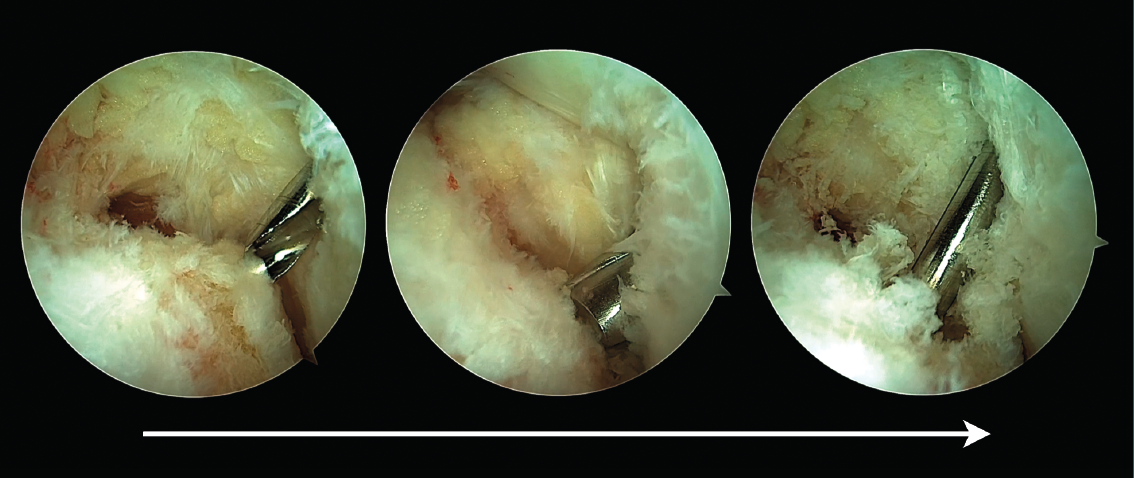

De acuerdo con las zonas descritas del tendón FHL(11), el tendón puede seccionarse en la zona 1 o 2. En la zona 1, el tendón se secciona justo antes de su entrada en la vaina fibro-ósea y con la ayuda de un bisturí o tijeras artroscópicas introducidas a través del portal endoscópico posterolateral. Alternativamente, el FHL puede seccionarse en su zona 2 a su paso bajo el sustentaculum tali. En este último caso, el artroscopio debe introducirse en la vaina fibro-ósea del tendón de FHL y, bajo visión artroscópica directa, el tendón se secciona con la ayuda de un bisturí de cirugía percutánea (bisturí de percutánea número 64) (Figura 3).

Figura 3. Sección del tendón flexor hallucis longus (FHL) en la zona 2. El artroscopio es introducido en la vaina fibro-ósea del tendón de FHL, el punto de sección es identificado con una aguja (visión superior), después es seccionado con un bisturí de cirugía percutánea (visión inferior).

Una vez que el tendón es seccionado, se externaliza a través del portal endoscópico posteromedial para pasarle una sutura que permita la tracción tendinosa. Se recomienda realizar una sutura de Krackow con un hilo de alta resistencia (Figura 4).

Figura 4. El tendón del músculo flexor hallucis longus (FHL) es externalizado por el portal posteromedial y se realiza una sutura de Krackow con un hilo de alta resistencia.